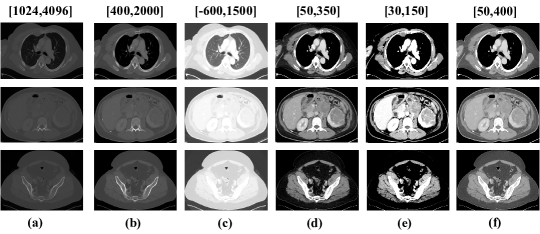

Figure 2: The top, middle, and bottom rows have CT-slices of chest-region, abdomen-region, and pelvic-region, respectively. The column (a) illustrates images with commonly used HU window (U=[1024,4096])𝑈10244096(U={[1024,4096]}) while columns ranging from (b) to (f) have images with our new 555 HU windows. The figure clearly demonstrates that by using more number of windows, different organs of a particular body-region present in a CT volume, can be highlighted more efficiently.)

• Multiple Intensity Image Generation: In general, the intensity of a CT-slice is re-scaled using a certain HU window, U𝑈U (e.g., a single and wide window of [1024,4096]10244096[1024,4096]) in order to include gray-scale intensities of different organs [Tang et al.(2019), Yan et al.(2018a)]. However, using a single window suppresses organ-specific information resulting into a degenerated image-contrast, as shown in Figure 2(a), which in turn makes it hard for the network to learn to focus on various organs present in the given CT volume. During manual detection of lesions, radiologists adjust these intensity values to focus on organs/tissue of interest [Bae et al.(2005)]. We exploit this domain knowledge and propose to feed it to the deep network explicitly in the form of CT-slices having multiple intensities which highlight different organs of the body. In a previous method by Zihao Li et al. [Li et al.(2019)], a clustering algorithm is used to determine three HU windows. In this paper, we incorporate this multi-organ information in input CT-slices by introducing five novel HU windows which are determined in such a way that the major body organs are covered. The proposed HU windows, as inspired by Masoudi et al. [Masoudi et al.(2021)], which cover almost all organs of interest for radiologists are: U1=[400,2000]subscript𝑈14002000U_{1}={[400,2000]}, U2,3=[600,1500],[50,350]subscript𝑈23600150050350U_{2,3}={[-600,1500],[50,350]}, U4=[30,150]subscript𝑈430150U_{4}={[30,150]}, U5=[50,400]subscript𝑈550400U_{5}={[50,400]} for bones, chest region including lungs & mediastinum, abdomen including liver & kidney, and soft-tissues, respectively. For a U=[Ul,Uw]𝑈subscriptUlsubscriptUwU=[\textbf{U}_{\textbf{l}},\textbf{U}_{\textbf{w}}], where, UlsubscriptUl\textbf{U}_{\textbf{l}} and UwsubscriptUw\textbf{U}_{\textbf{w}} are the window level/center and window width, the intensity values of a CT-slice are first normalized using Ul±Uw/2plus-or-minussubscriptUlsubscriptUw2\textbf{U}_{\textbf{l}}\pm\textbf{U}_{\textbf{w}}/2 as data min/max & clipped between [0,1]01[0,1] and then, re-scaled to values in [0,255]0255[0,255].